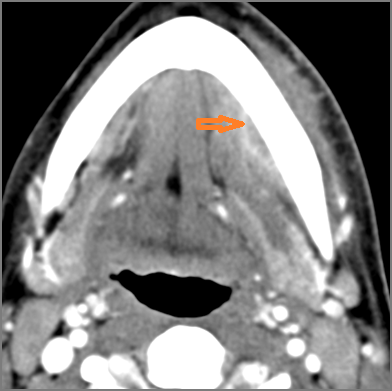

Oral Cavity, Floor of the Mouth, Maxilla and Mandible

There is excessive enhancement or thickening of the fat or other soft tissues within or surrounding the buccal space, masticator space, floor of the mouth, submandibular space or the adjacent superficial fascia or subcutaneous fat and skin. [Yes/No]

There is subperiosteal abscess or an abscess cavity adjacent to or involving the maxilla or mandible. [Yes/No]

There is endodontal or periodontal disease that might be causing cellulitis or abscess. [Yes/No]

There is edema/abscess within the fat of the adjacent parapharyngeal and retropharyngeal space. [Yes/No]